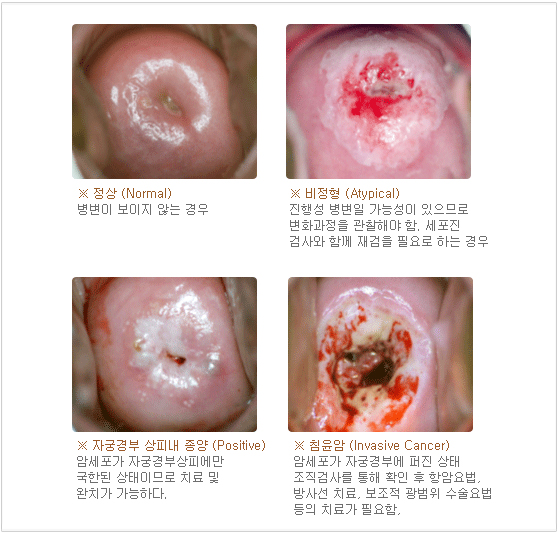

�ֽ� ���� �ػ� ������ ���� �ڱð�κ����� �߰��ϰ� �����˻���� ������ ����Դϴ�. ���� ��Ȯ�� ����� �˱� ���ؼ��� �ڱ� ����� ���Ҹ� Ȯ�� �����ϴ� ��Ȯ��� �˻縦 �ϰ� �˴ϴ�. ���� �δ���� ������ ������ �� ������ ������ �˻�� ����� 98%������ ��Ȯ���� ��Ÿ���ϴ�.

�ֽ� ���� �ػ� ������ ���� �ڱð�κ����� �߰��ϰ� �����˻���� ������ ����Դϴ�. ���� ��Ȯ�� ����� �˱� ���ؼ��� �ڱ� ����� ���Ҹ� Ȯ�� �����ϴ� ��Ȯ��� �˻縦 �ϰ� �˴ϴ�. ���� �δ���� ������ ������ �� ������ ������ �˻�� ����� 98%������ ��Ȯ���� ��Ÿ���ϴ�.

�ڱð�ο� ���� ��θ� �ʻ����� ó���� �� �ʻ��� ������ ���̴� ��Ҹ� Ȱ���� �� ������ ���� �ǵ��ڰ� �м��ϴ� ������ �ǵ��ڴ� ����� �Ⱓ�� ������ ���� ������ ���ΰ� ������ �� Colposcopy ������ �������Դϴ�.